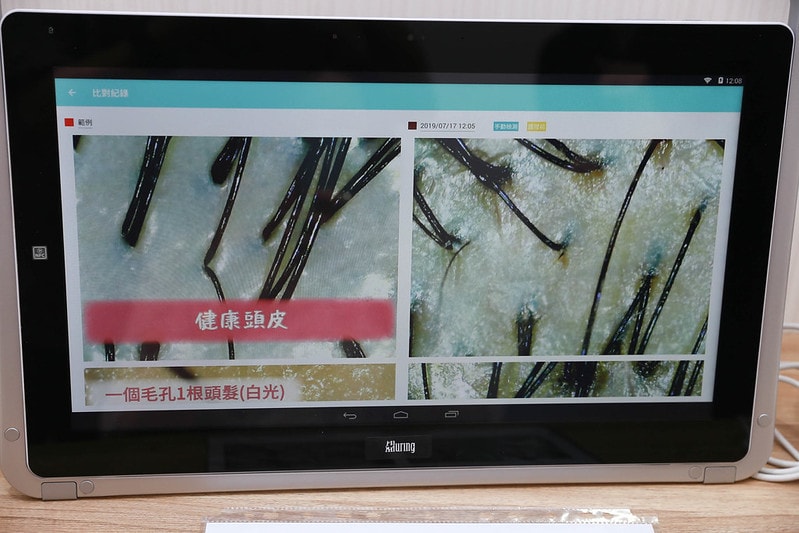

頭皮放大倍數分析檢測

頭皮放大倍數分析檢測

整個頭皮問題都被一覽無遺~

其實頭皮被這麼放大倍數看真的很羞恥XDDD

左邊的照片是健康的頭皮示意圖

右邊是我的頭皮檢測實品圖

可以發現一天沒有洗頭油脂分泌

還有角質堆積比較嚴重

代謝變慢導致頭皮外油內乾

使皮脂堆積阻塞頭皮毛孔上無法讓頭皮深呼吸

頭皮肌底需要好好活絡跟活化毛囊

才能再度恢復健康的頭皮

而且泛紅的地方也滿多的

像我就是因為一兩個月就漂髮一次

除了對髮質傷

當然對於頭皮也是會有影響的

會比其他沒有漂頭髮的人來得敏感